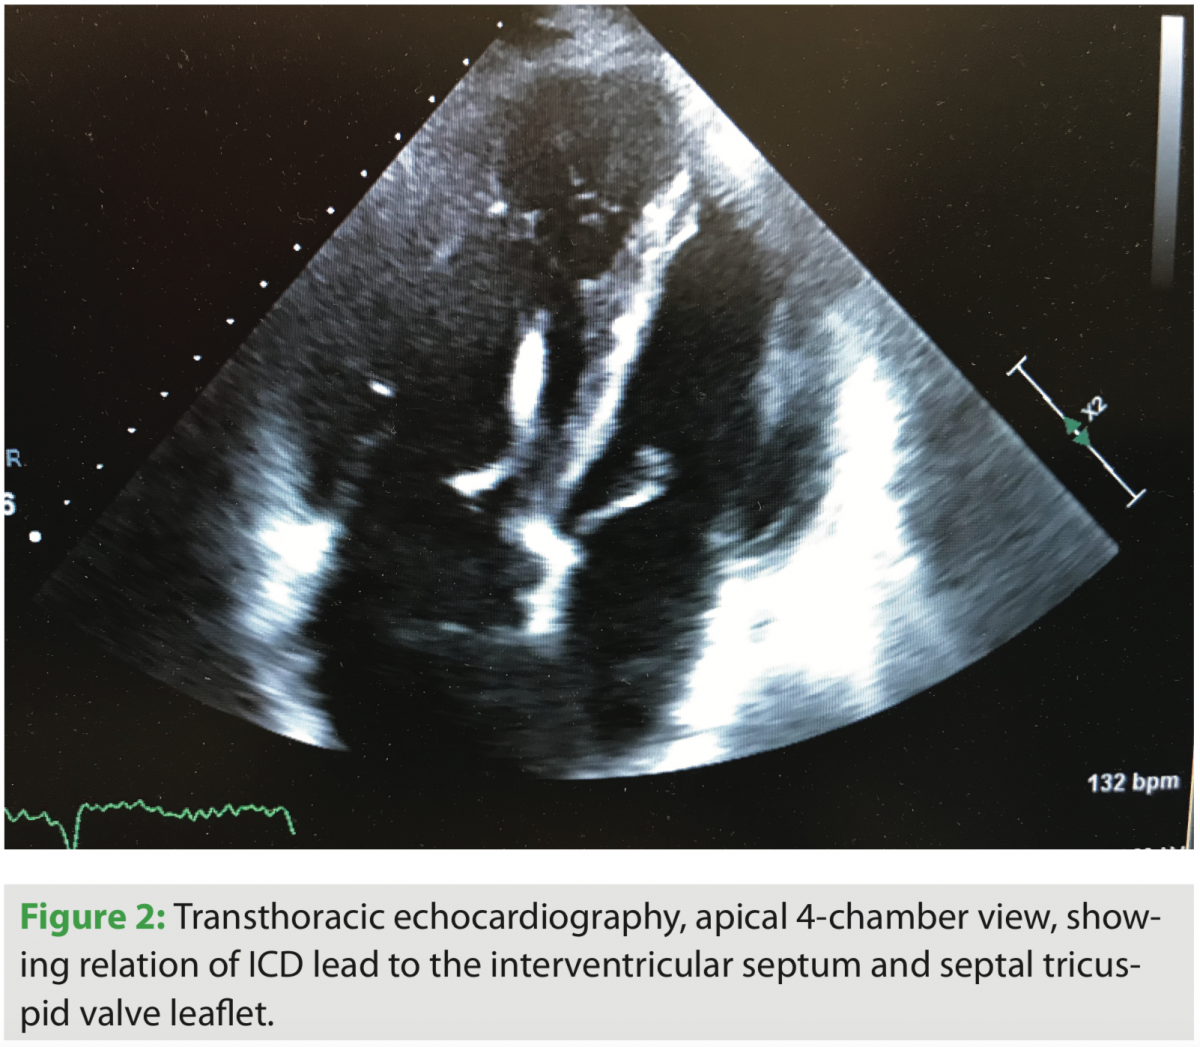

After admission and diuresis, significant symptomatic improvement occurred, and the patient was nearing his perceived dry weight based on initial clinic visits and recorded weights from home. Standard two- and three-dimensional transthoracic echocardiography were performed, and significant tricuspid valve regurgitation was seen. The course of the right ventricular lead can be seen in several views, along with its interaction with the TV leaflet and interventricular septum (Figures 1, 2, and 4). Corresponding tricuspid valve dysfunction is appreciated with severe tricuspid valve regurgitation on Doppler echo images (Figures 3 and 5). The RV was felt to be moderately dilated with a mid-RV diameter of 3.5 cm. Significant RV systolic dysfunction was seen and felt to be moderate with a tricuspid annular plane systolic excursion (TAPSE) of 1.25 cm. The tricuspid valve regurgitation was severe with a vena contracta width of 0.9 cm and PISA radius of 1.0 cm. LV systolic function was essentially unchanged, with an EF of 25%. The bioprosthetic aortic valve was well seen and without significant dysfunction.